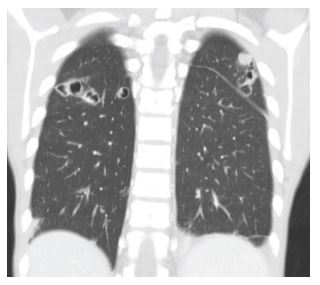

A previously healthy 16-year-old male presented to the Emergency Department with a 10-day history of edema and pain in the left upper eyelid and complaints of pain in the left thigh. He had no fever. On examination, erythema and edema with fluctuation of the left upper eyelid and frontal region were observed associated with proptosis and blurred vision. Additionally, he had edema, redness, heat and pain, and claudication in the left thigh and gluteal region. There were no signs of trauma, insect bites, or foreign bodies. The boy denied illicit drug use, namely intravenous use. Blood tests revealed leukocytosis (33,700 cells/μL) with neutrophilia (30,600 cells/μL) and elevated C-reactive protein (303 mg/L). Creatine kinase was normal. Computed tomography (CT) scan showed a multiloculated collection in the muscle planes of the thigh (Figure 1) and a partial thrombus in the left femoral vein. It also showed an expanding intraorbital lesion with proptosis and optic nerve extension (Figure 2). Empiric antibiotic therapy with ceftriaxone, clindamycin, and vancomycin was initiated, and the patient underwent surgical drainage of the intraorbital abscess and deep loculated collection in the left thigh. Methicillin-susceptible Staphylococcus aureus was isolated from blood and exudate cultures. During hospitalization, the boy remained persistently febrile despite analytical improvement. Thoracic, abdominal, and pelvic high-resolution CT scans were performed on day 8, showing bilateral cavitary lung lesions (Figure 3).

Figure 3 Chest CT scan on day 8 of hospitalization showing bilateral cavitary lung lesions suggestive of septic embolism.